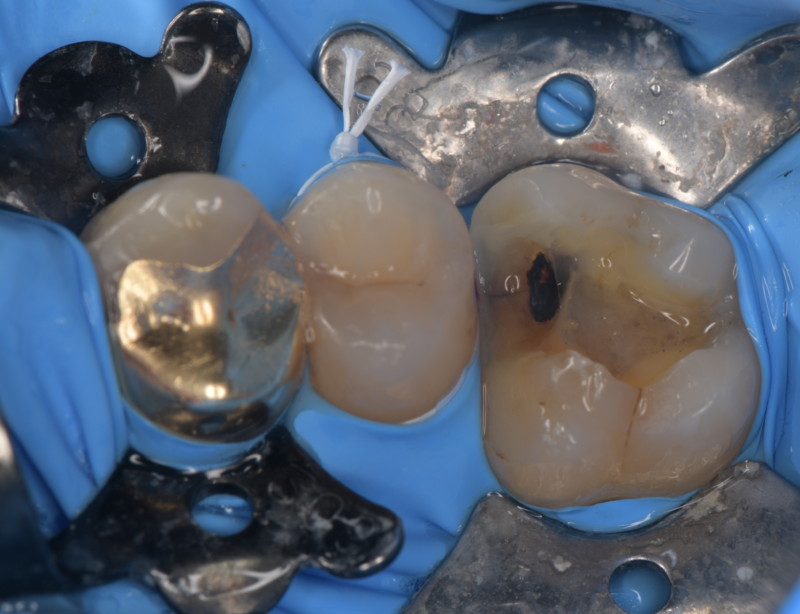

患者さんは歯がとても沁みると訴える歯医者さんでした。適切な治療を受け、セルフケアやメンテナンスを完璧にしているはずの歯医者さんでも虫歯になる事があります。 その原因は噛み合わせや生活習慣です。負荷の大きな力から歯のひび割れ(マイクロクラック)が起こり、その間を伝って細菌に栄養が運ばれ、知らないうちに進行してしまいます。 顕微鏡を使い、ひび割れを取っていきます。このひび割れが残っていると再び、細菌の感染経路となるため、可能な限りとります。これは十分な治療時間と顕微鏡がなければ不可能な仕事です。   虫歯を取っていくと神経の露出が見られました。 MTAセメントにて神経保存を行いました。 だんだんと、症状が改善してきたそうなので、今後、最終修復を行う予定です。       リスク 極端に硬いものを噛むと取れたり、かける可能性があります。 ラバーダム、顕微鏡等を使用し適正な時間を確保された治療は自由診療となります。 各種治療費はこちらから